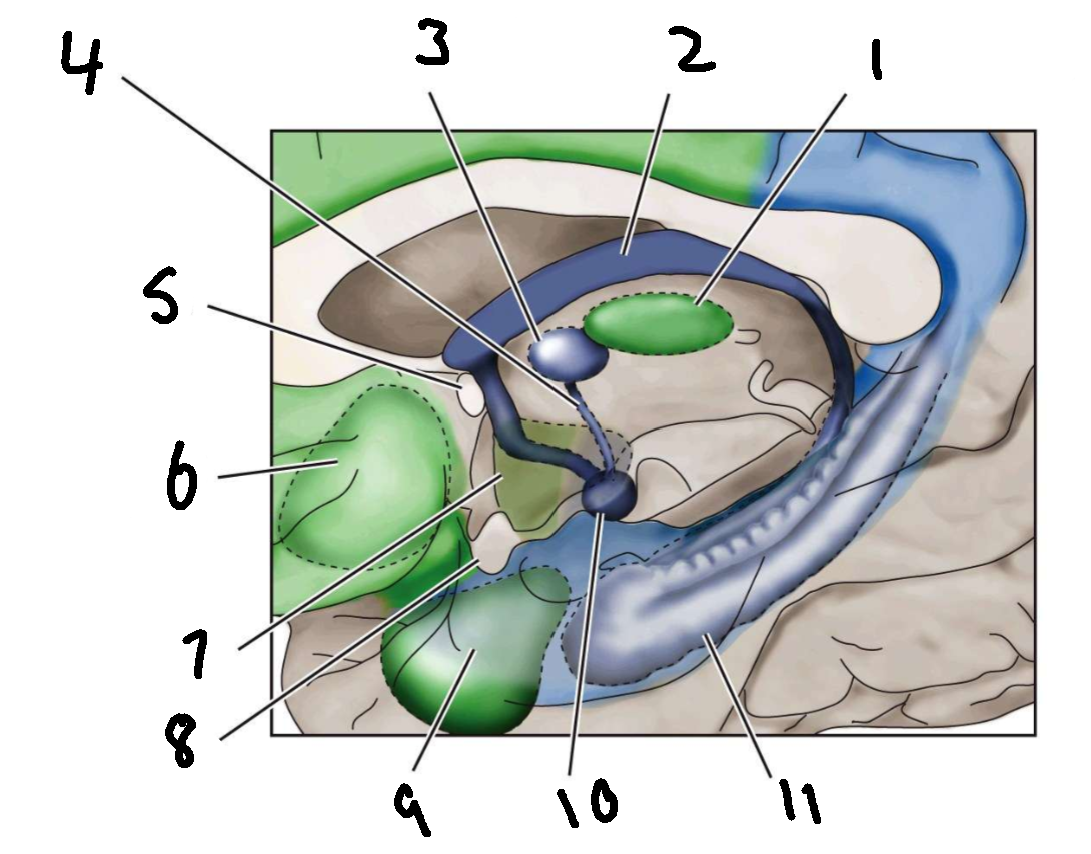

What is 1?

mediodorsal nucleus of the thalamus

What is 2?

fornix

What is 3?

anterior nucleus of the thalamus

What is 4?

mammillothalamic tract

What is 5?

anterior commissure

What is 6?

ventral basal ganglia

What is 7?

hypothalamus

What is 8?

optic chiasm

What is 9?

amygdala

What is 10?

mammillary body

What is 11?

hippocampus